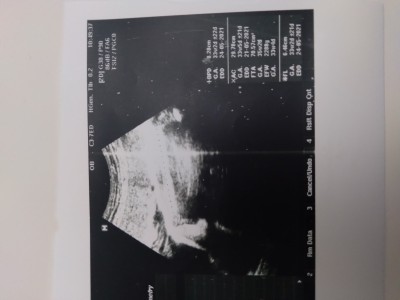

34+1 resimli rica etsem bakarmısınız

hanımlar bebeğin boyu nerde yazıyor boyu kc cm acaba anlayan var mi varsada boyu haftasina göre iyimi acaba

34+1

Net okunmuyo canm FL yazan yeri 7 ile çarpınca boyu cikiyo

Fl yazan yer doğru gördüysem 6.46 7 ile çarpınca sonuç 45.22 çıkıyo ama bi doktorunuza da sorun derim

Yanlış okumadıysam fl 7 ile çarptım 44.5 45 cm civarı bebeğiniz

Diğer anneler de demiş zaten ama FL yazan yer 7ile çarpılınca boyu hesaplanıyor. Boyu da normal sanırım haftasına göre. Yine doktorla teyit edin tabi.